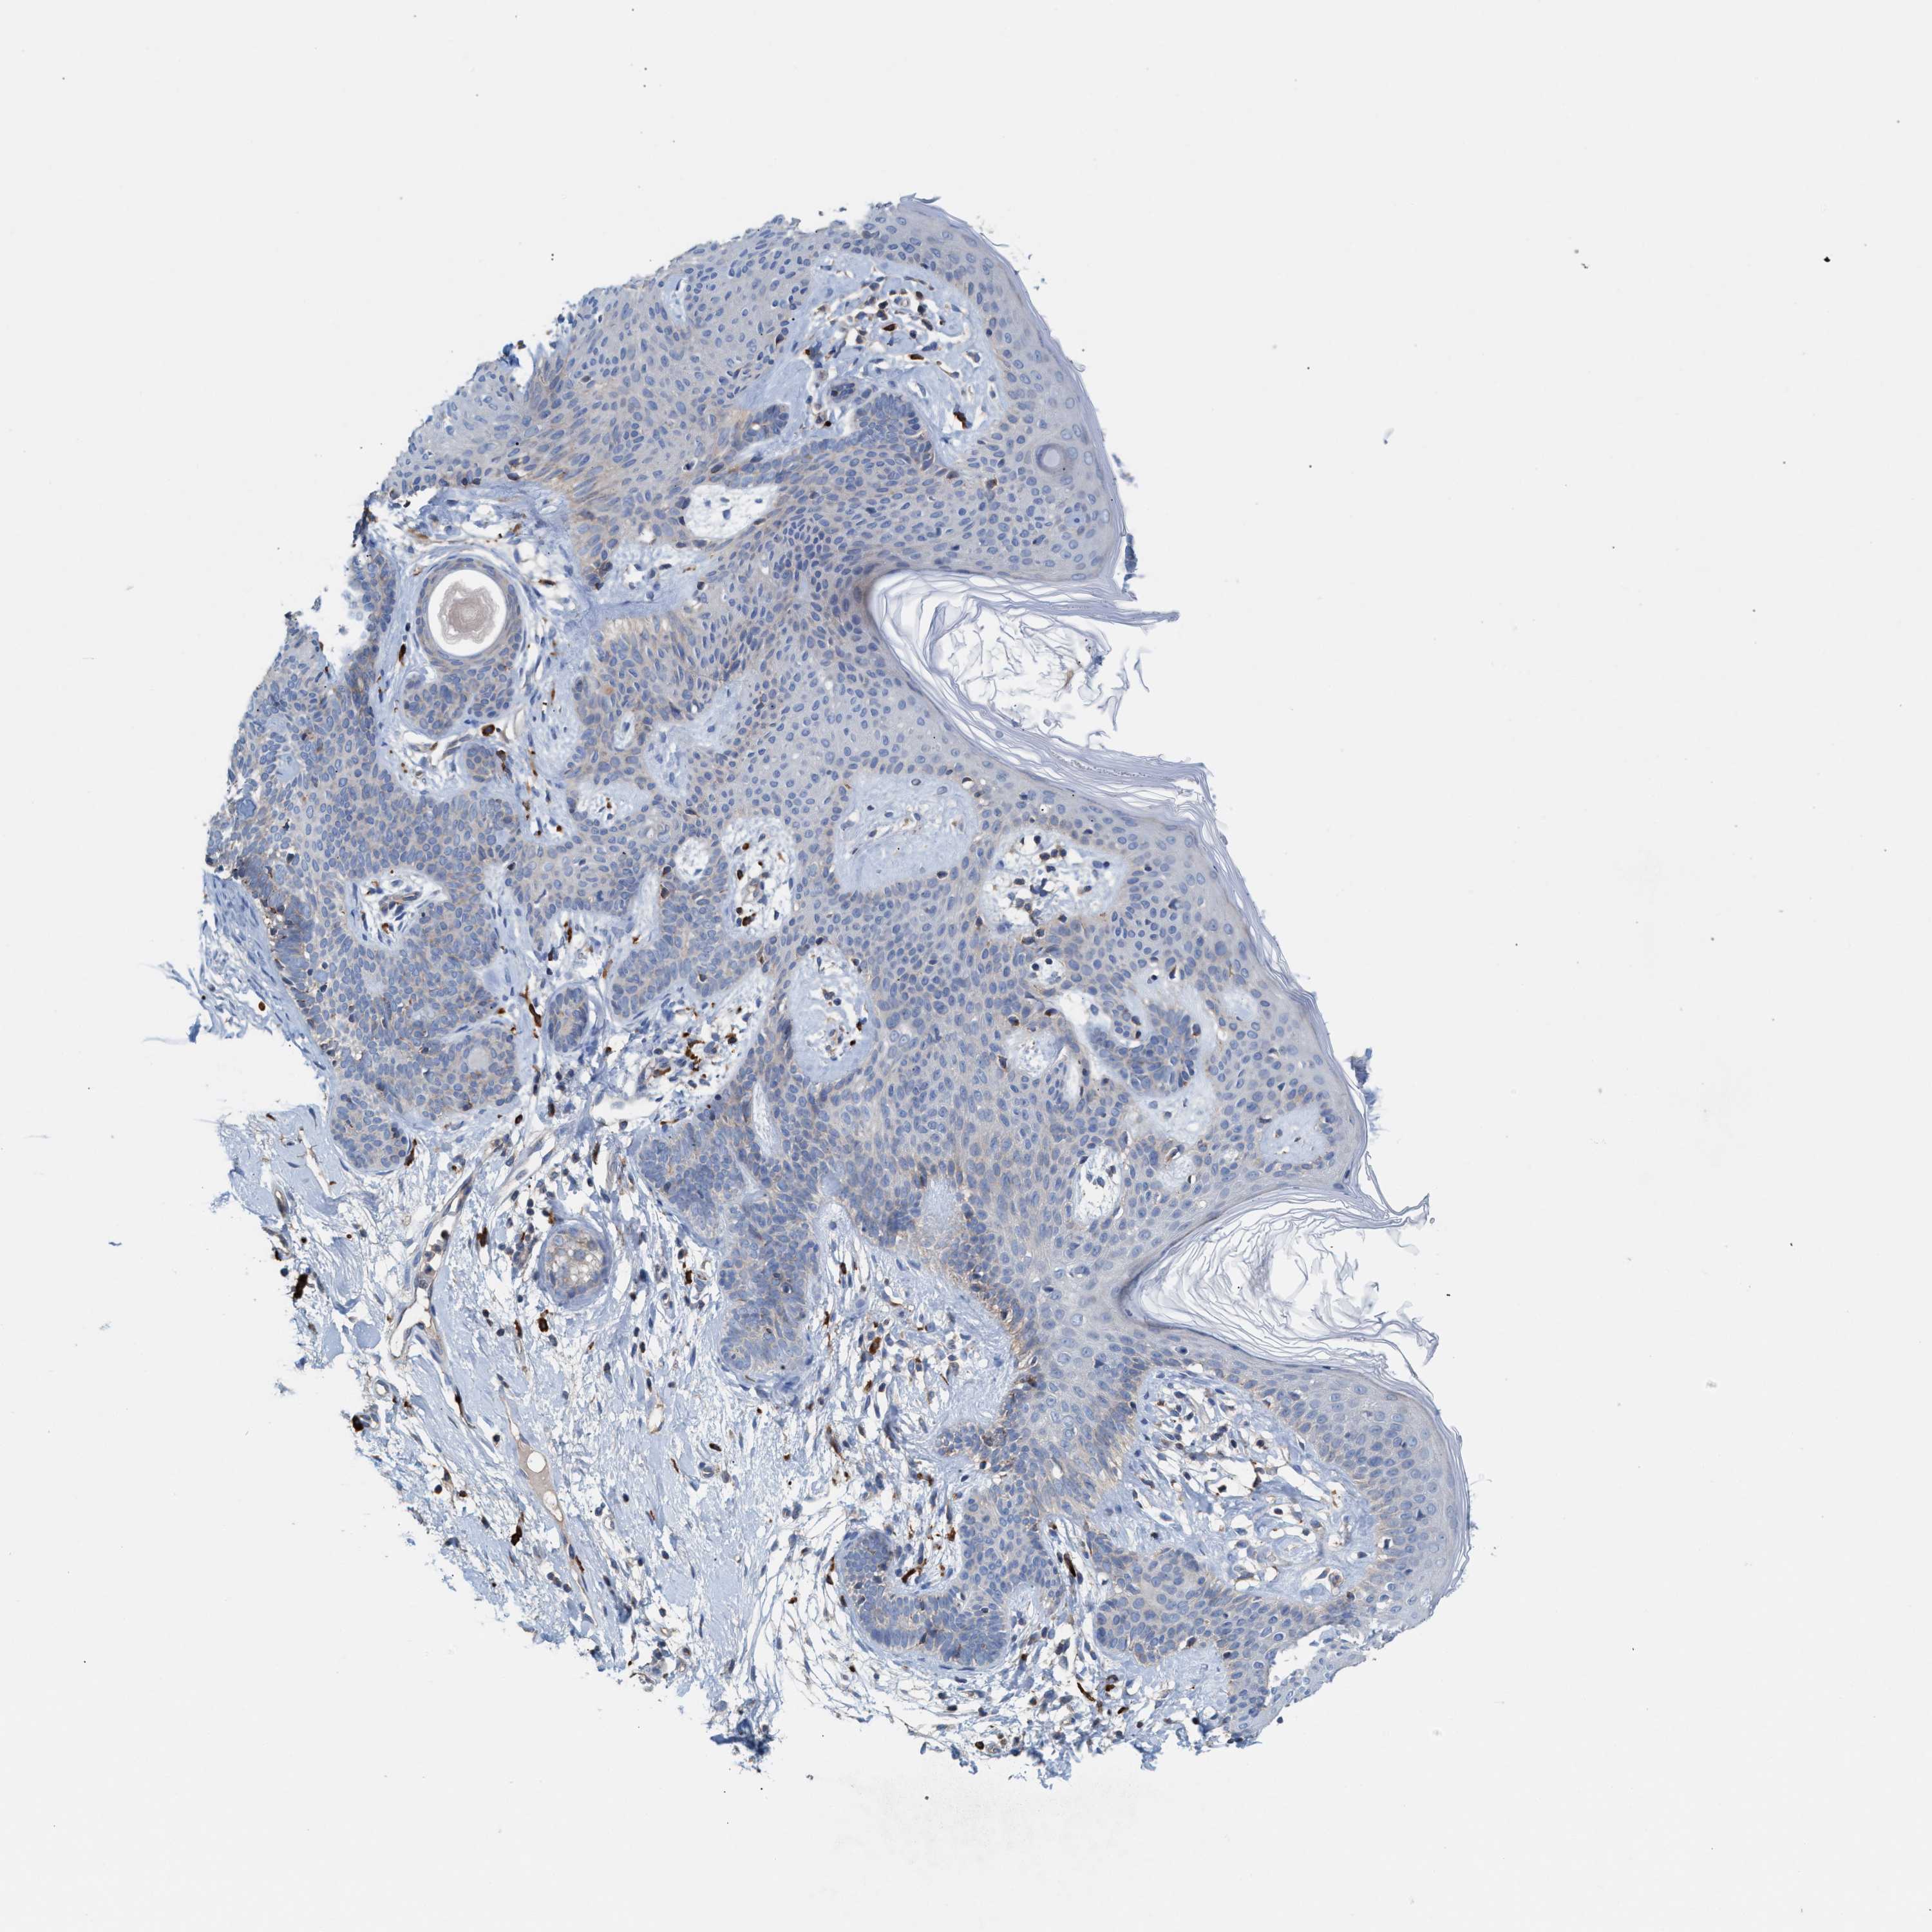

CANCER SKIN CANCER Show tissue menu

SKIN CANCER - Protein expressioni

A mouse-over function shows sample information and annotation data. Click on an image to view it in a full screen mode. Samples can be filtered based on level of antibody staining by selecting one or several of the following categories: high, medium, low and not detected. The assay and annotation is described here.

Each image is clickable and will lead to virtual microscopy that enables deeper exploration of all samples and also displays staining intensity scores, fraction scores and subcellular localization as well as patient and tissue information for each sample.

Antibody HPA021598

Staining

High

Medium

Low

Not detected

Intensity

Strong

Moderate

Weak

Negative

Quantity

>75%

75%-25%

<25%

None

Location

Nuclear

Cytoplasmic/membranous

Cytoplasmic/membranous,nuclear

Squamous cell carcinoma in situ, NOS

Squamous cell carcinoma, NOS

Squamous cell carcinoma, metastatic, NOS

Basal cell carcinoma

Adnexal tumor, benign